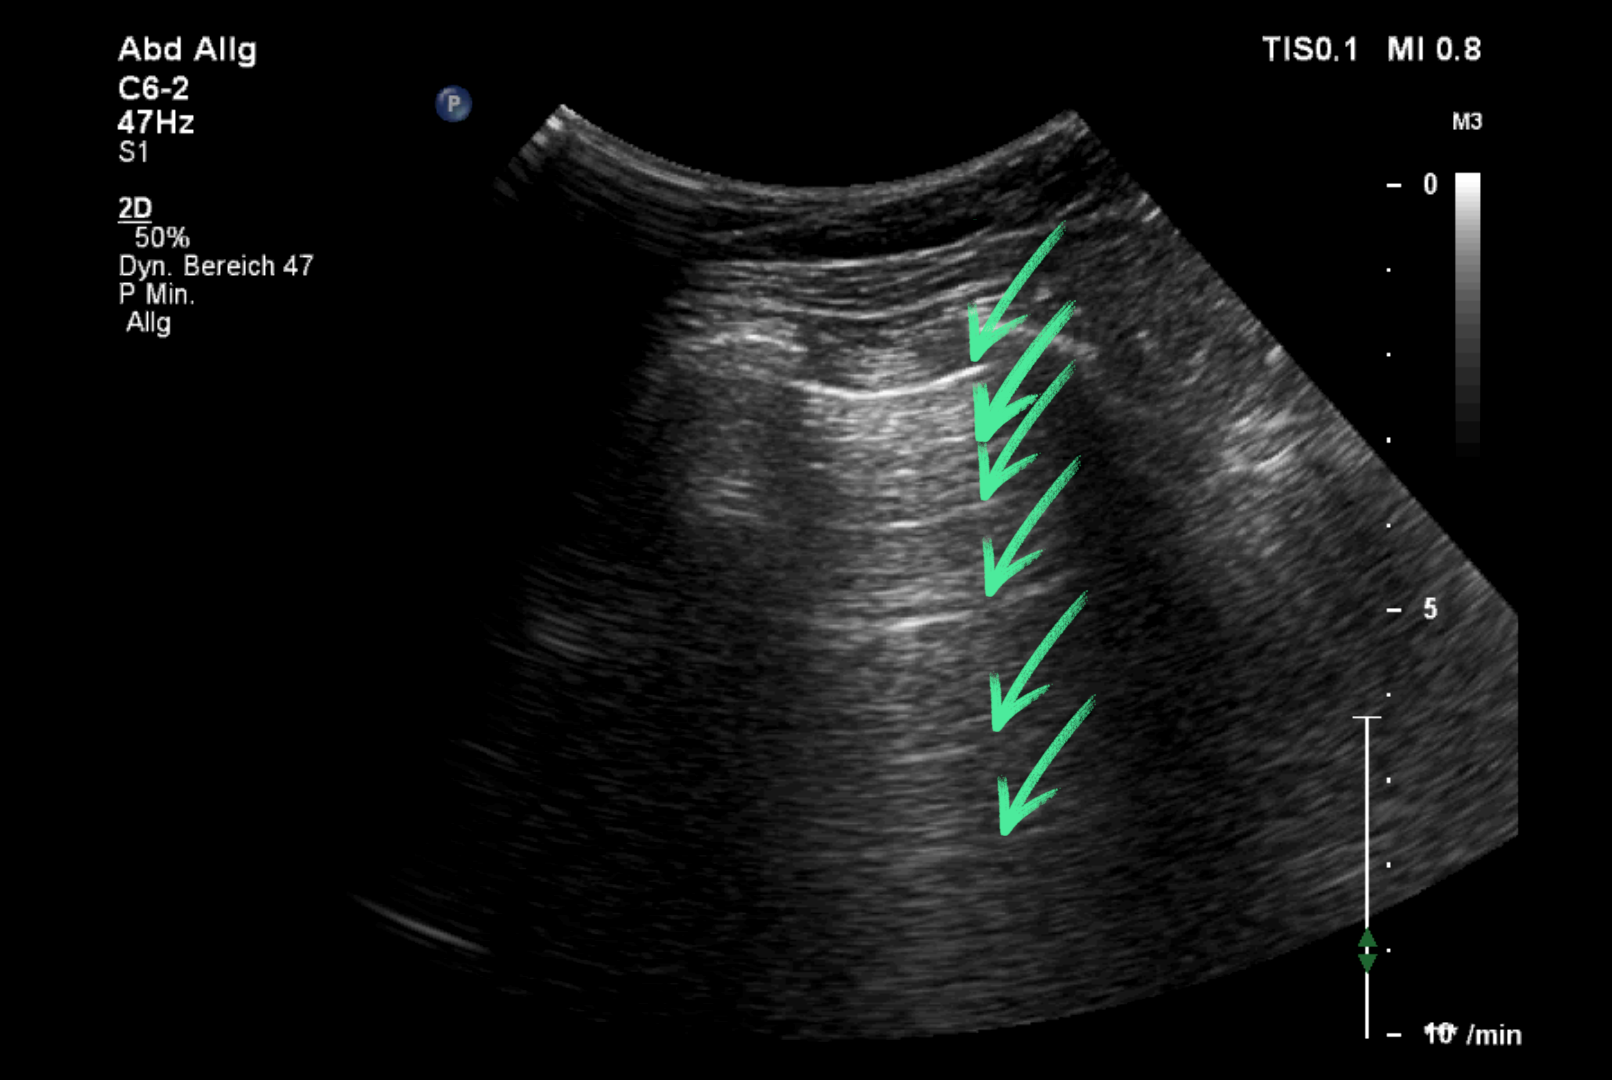

einfache Reverberationen (Wiederholungsechos)

Echos aus der Gewebetiefe können zwischen Gewebe-Grenzflächen mehrfach hin und her reflektiert werden, bevor sie wieder auf den Schallkopf treffen. Dadurch kann die gleiche anatomische Struktur mehrfach zur Darstellung kommen.

Lungensonographie::

Die parallel zur Pleura parietalis verlaufenden, in regelmäßigen Abständen zur Pleuralinie auftretenden, echoreichen Linien sind verursacht durch Reverberationen der Pleura parietalis.